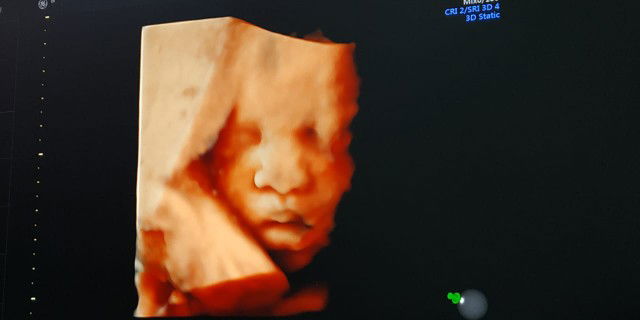

usg 4d

Seneng bgt liat dedek jadi gasabar pengen gendong karna anak pertama umur 8th udah jarang main sama mamanya ? tp sedih karna kmrn wktu usg uk 35w3d tp berat baru 2015g katanya kecil ,trs hb ku cuma 9 ? 10 hari lagi suruh cek darah lagi kalo hb ga naik ke 11 harus transfusi darah ? mohon doanya ya bunda biar hb ku naik dan dedek beratnya nambah banyak ?